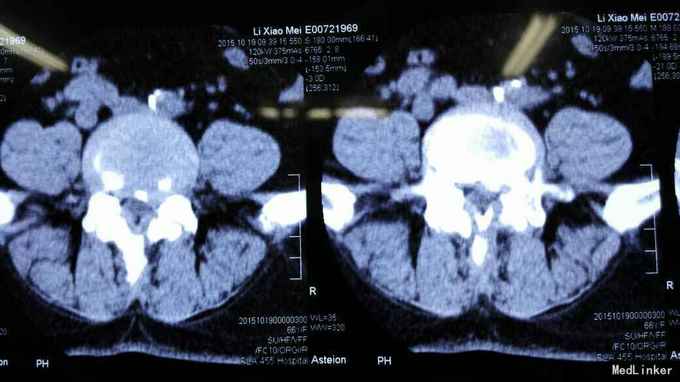

查体符合腰5神经根受压体征。腰椎CT、MRI提示腰4/5椎间盘突出,椎管狭窄。

考虑腰椎间盘突出伴椎管狭窄症。行椎间孔镜下髓核摘除,椎间孔成形。